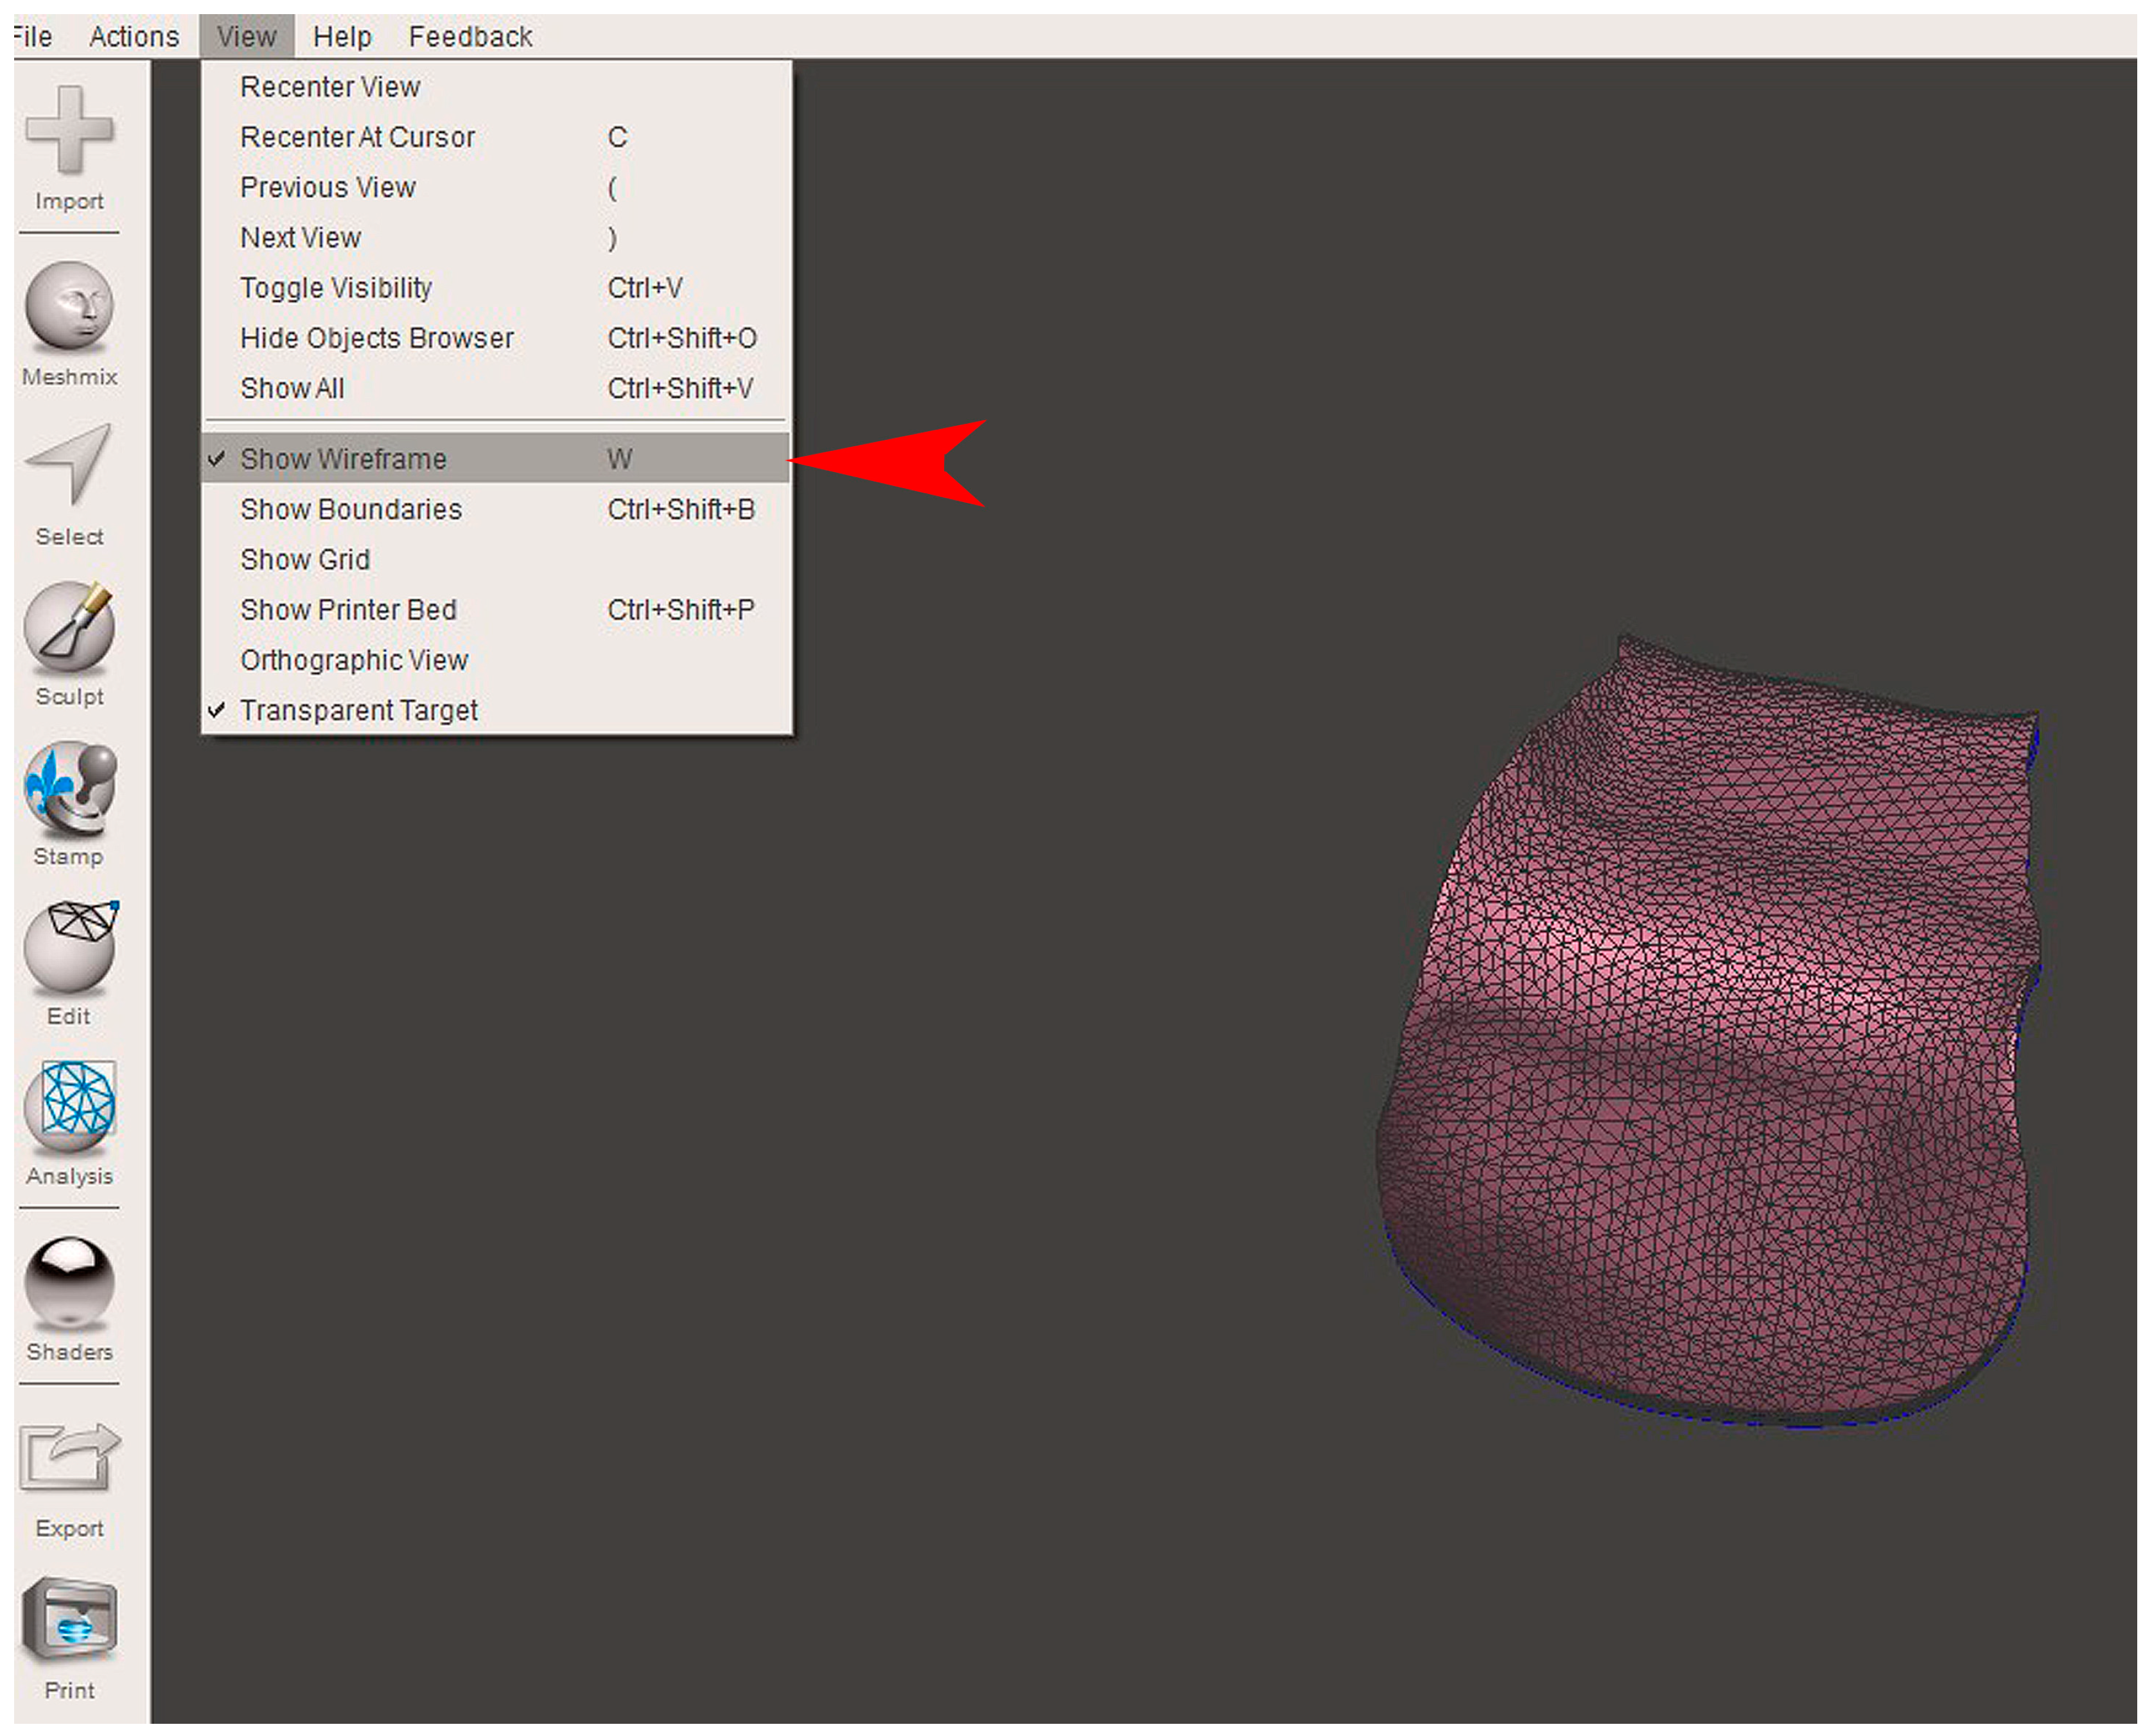

2.2. GBR Simulation and Mesh Design